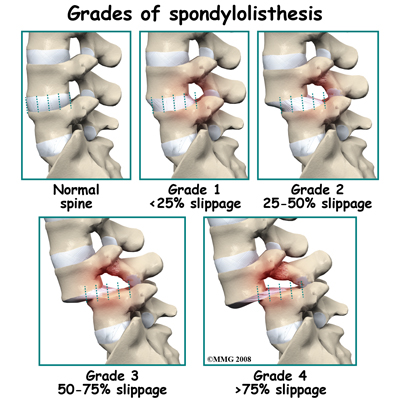

A condition called spondylolysis can lead to the slippage that happens with spondylolisthesis. Spondylolysis is a defect in the bony ring of the spinal column. It affects the pars interarticularis, mentioned earlier. This defect is most commonly thought to be a stress fracture that happens from repeated strains on the bony ring. Participants in gymnastics and football commonly suffer these strains. Spondylolysis can lead to the spine slippage when a fracture occurs on both sides of the bony ring. This slippage is called spondylolisthesis. The slippage is from I through IV, one being mild, IV often causing neurological symptoms. The back section of the bony ring separates from the main vertebral body, so the injured vertebra is no longer connected by bone to the one below it. In this situation, the facet joints can't provide their normal support. The vertebra on top is then free to slip forward over the one below.

With cases of lumbar spondylolisthesis, doctors will usually order of the low back. The X-rays are taken with your spine in various positions. They can be used to see which vertebra is slipping and how far it has slipped.